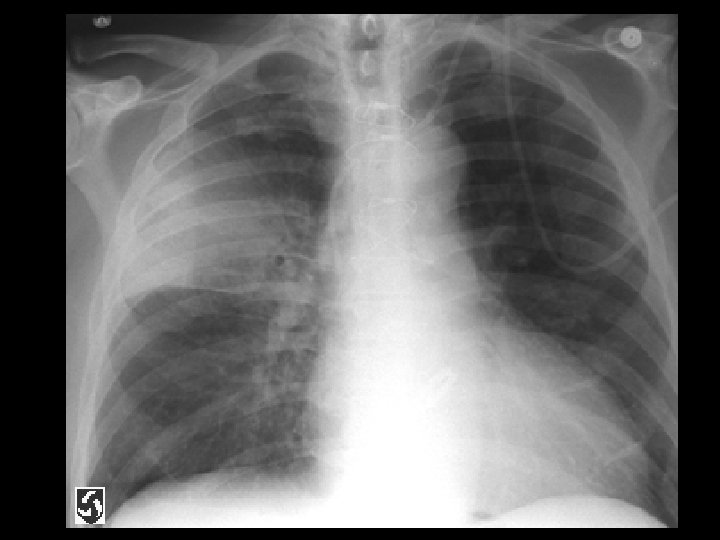

Left hydropneumothorax • Findings: – left pnuemothorax – left pleural effusion (possibly blood) • causes: – penetrating trauma – iatrogenic – bronchopleural fistula